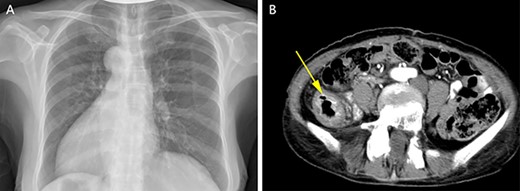

A physical examination revealed that the abdomen is flat, without gastrointestinal type and peristaltic wave, and the right lower abdomen has mild tenderness, with no rebound pain and muscle tension, and the mass can not be touched. Serum tumor markers were not elevated (CEA 2.3 ng/ml and CA-199 4.15 ng/ml). The laboratory examination confirmed mild anemia and hypoproteinemia. Abdominal computerized tomography (CT) showed the apex of the heart on the right side, the liver on the left side of the abdominal cavity (Fig. 1A), the stomach and spleen on the right side of the abdominal cavity (Fig. 1B), confirming SIT. In addition, the chest X-ray confirmed the apex of the heart on the right chest (Fig. 2A), and abdominal CT indicated that the tumor (stage T4N0M0) was located in the descending colon (Fig. 2B).

Enhanced CT of the upper abdomen showed that the heart was located on the right side of the thoracic cavity, the liver was located on the left side of the abdominal cavity (A), and the stomach and spleen were located on the right side of the abdominal cavity (B), confirming SIT.